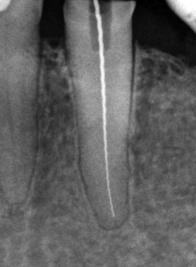

perfekte Wurzelkanalfüllung